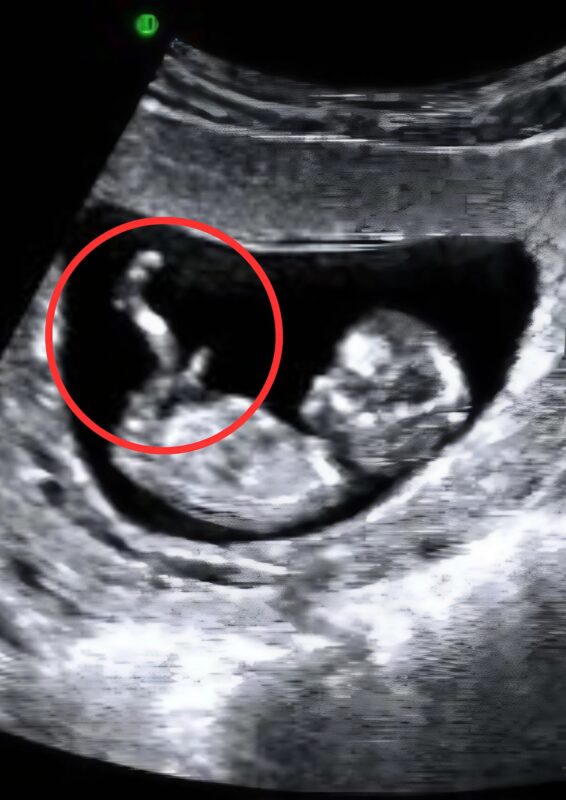

The screen flickered to life, showing the familiar shapes and movements of my little one 👣. I smiled faintly, hoping to see a healthy, kicking baby. But then the doctor’s expression changed. His brow furrowed, and he was silent for a long moment. My smile faltered 😳.

He looked at me with a mixture of sympathy and concern 😔. “There’s… a problem,” he said carefully. “Your baby… your baby doesn’t have a leg.”

I sat there, staring at the screen. My baby was moving, waving tiny arms, and I could see the little heart beating rapidly ❤️. Even though something was missing, the life inside me was perfect in its own way. My mind began to race with questions: “How will I raise this baby? Will they face challenges? Will I be able to protect them?”